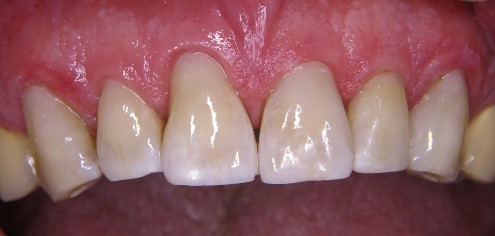

Efekt ostateczny odbudowy zębów przednich był w tym przypadku wyjątkowo zadowalający (ryc. 15). Sytuacja początkowa przed rozpoczęciem leczenia wykazała niezadowalające i przebarwione wypełnienia w odcinku od zęba 13 do 23. Wybór nowego materiału VisCalor i wykorzystanie technologii konsystencji zależnej od temperatury umożliwił wykonanie bardzo estetycznej i oszczędnej dla tkanek rekonstrukcji techniką bezpośrednią podczas zaledwie jednej wizyty. Porównanie sytuacji przed i po uwidacznia istotną poprawę zarówno kształtu, jak koloru. Po wypolerowaniu na wysoki połysk i fluorkowaniu preparatem Bifluorid 10 (VOCO GmbH, Cuxhaven) widoczny był natychmiast indywidualny, estetyczny i naturalny efekt.

Ryc. 15. Ostateczna odbudowa z materiału VisCalor.